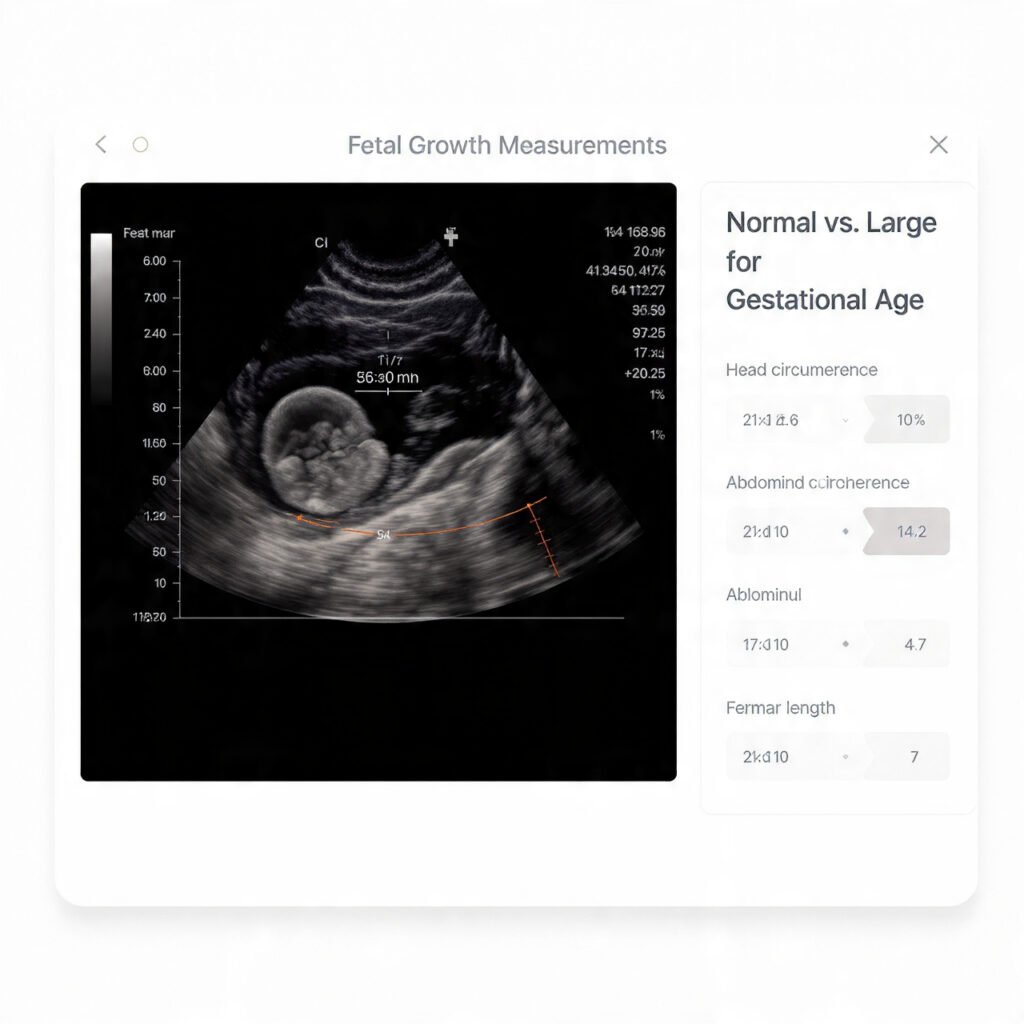

How Is LGA Diagnosed?

At Nisarga Diagnostics, LGA is diagnosed using advanced pregnancy growth scans that include:

• Estimated fetal weight calculation

• Measurement of baby’s head circumference

• Abdominal circumference (very important for detecting sugar-related growth)

• Femur length

• Comparison with gestational age charts

These measurements help radiologists and doctors determine whether the baby is growing appropriately or is larger than expected.